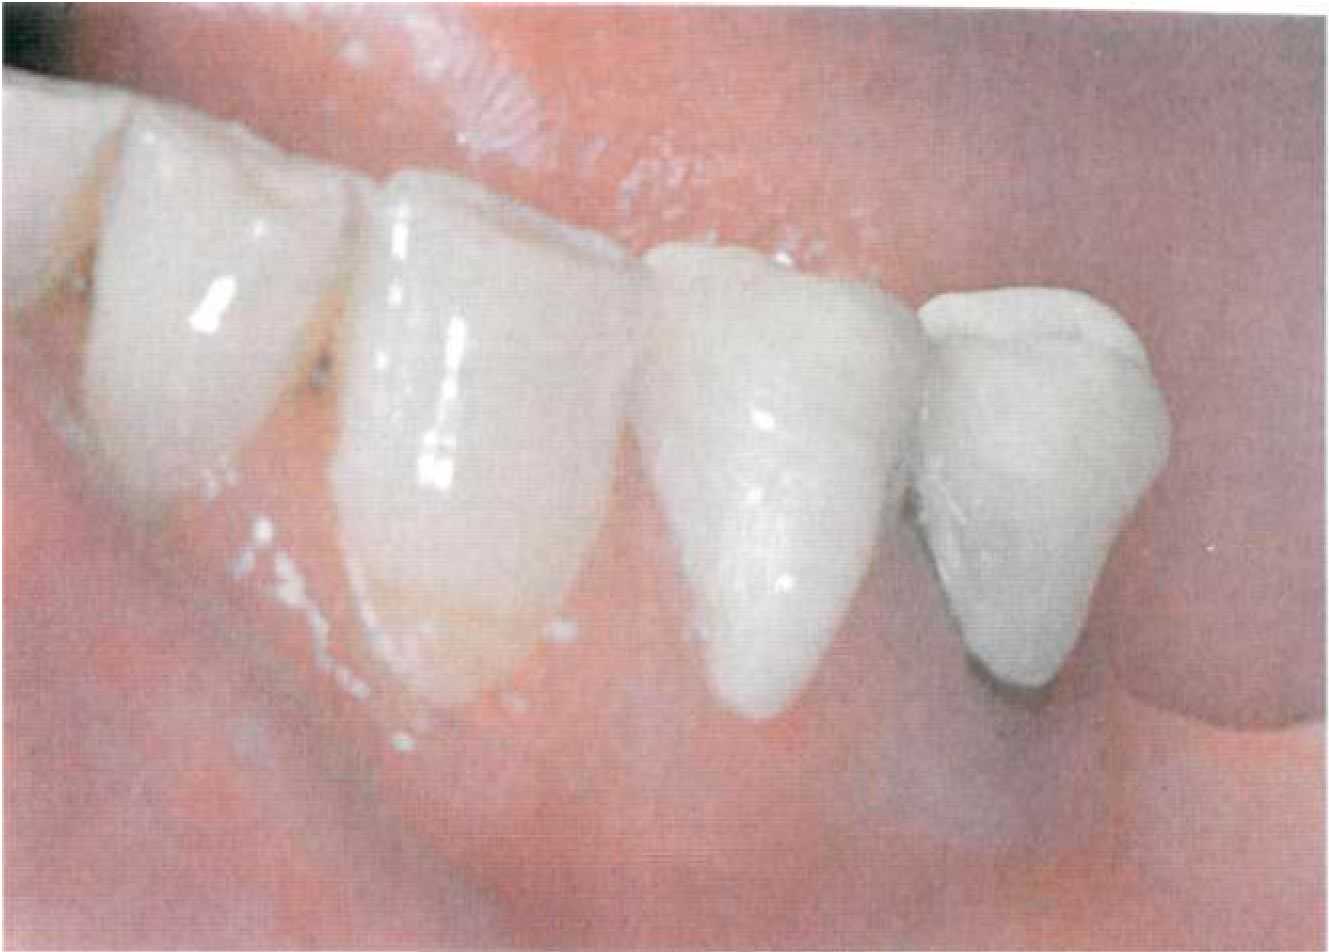

Этап 5. После нанесения зубным техником керамической облицовки в клинике проводят припасовку металлокерамических коронок опорных зубов (рис. 109). Выверяют окклюзионные контакты, цвет. Этап 6. После глазуровочного обжига коронки фиксируют в полости рта на корригирующий оттискной материал для избежания смещения (рис. 110) и снимают оттиск для изготовления съемной части комбинированного протеза. Возможно применение индивидуальной ложки, изготовленной по предварительному альгинатному оттиску. Опорные коронки с замковыми креплениями переходят в оттиск (рис. 111). Этап 7. В лаборатории опорные коронки заливают воском и по полученному оттиску изготавливают рабочую модель (рис. 112). К замковому креплению, установленному на опорных коронках, присоединяют комплементарную часть (рис.113) или ее аналог. В зависимости от типа замкового крепления и конструкции съемной части протеза модель дублируют или проводят моделировку каркаса на рабочей модели, используя беззольную пластмассу (рис. 114).